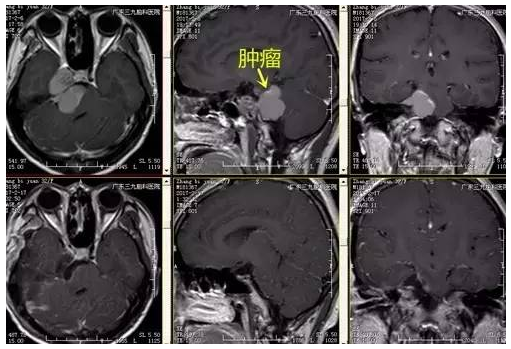

张女士,32岁,因右侧面部针刺样痛疼伴麻木持续2月余未有缓解,速来医院就诊,门诊CT提示右侧中后颅窝等密度影,收入住院治疗。入院后完善相关术前检查,术前DWI检查示右侧跨中后颅窝占位性病变呈低信号,术前磁共振示哑铃状病变,各序列以高信号为主高低混杂信号影,瘤体约4.5cm×3.7cm×3.3cm,完善检查后,行右侧中后颅窝占位性病变切除术,手术由神经一科主任张良主刀完成。术程顺利,术后患者恢复良好,未见并发症,术后MR提示肿瘤切除。

手术切除是治疗颅内皮样囊肿的唯一手段,应在保留神经血管的前提下,尽量切除肿瘤,肿瘤囊壁与重要脑组织、血管。神经黏附过度密切时,尽量不要尝试切除囊壁,虽然部分残留会引起术后复发,但复发率低,且生长缓慢,必要时可再次手术治疗。本例患者术后MR提示肿瘤全切除,术后恢复良好,未见明确并发症状。